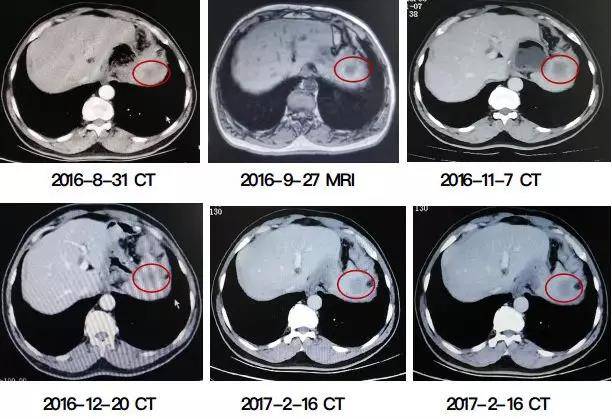

病情评估:肿瘤标志物(CA199)2016-6-27 48.02逐渐升高至2016-11-7 323.2U/ml。影像学CT(2016-8-31)肝左叶脾上缘处见1.8×1.5cm结节,边界模糊。MRI(2016-9-27)肝左叶外侧段见2.3×2.3×1.9cm信号欠均匀影。CT(2016-11-7)肝左叶脾上缘处见3.7×2.6cm结节,边界模糊。活检病理(2016-10-26):(肝脏肿瘤)腺癌,免疫组化CDX-2(+),Ki-67(60%) Her-2(2+),Fish结果为基因扩增。

客观疗效:肿瘤标志物(CA199)2017-2-3降至58.23U/ml。影像学CT(2017-2-16)肝左外叶转移瘤(2.3×2.3cm),缩小37%,达PR。见下图。